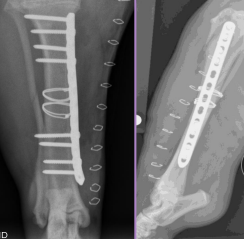

Interlocking Nail

What: IM pin + locking bolts proximal and distal

IM pin controls bending

Bolts control shear & rotation

Why: femur, tibia, humerus: limited to

$$, technically demanding, specialized

How:

Fills 80-90% of medullary canal

Place proximal and distal of break